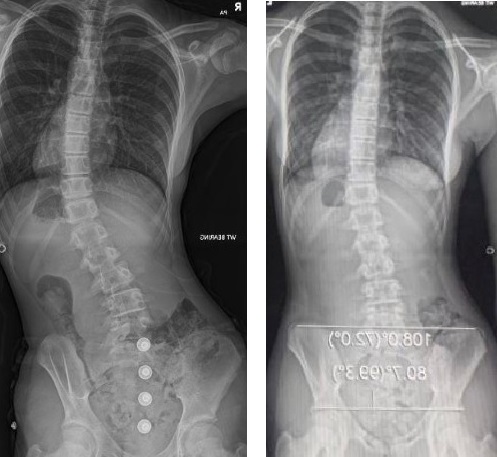

Измерение кифоза грудного отдела: Рентгеновские снимки